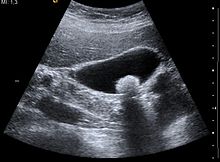

Πρόκειται για στερεούς σχηματισμούς εντός της χοληδόχου κύστεως ή των σωληναρίων τα οποία δεν επιτρέπουν την σωστή λειτουργία του οργάνου και σταδιακά αυξάνονται σε μέγεθος.